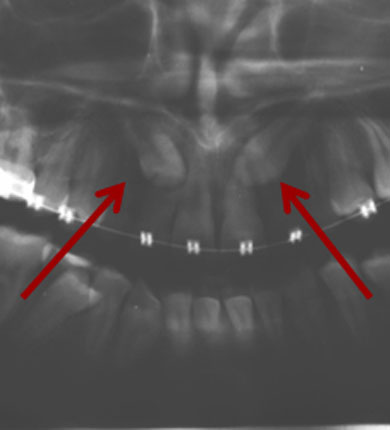

Gefahr der Nervverletzung bei der Weisheitszahnentfernung

Die Gefahr von Nervverletzungen können wir dadurch erheblich reduzieren!

Lagebestimmung von verlagerten Zähnen

Im normalen Röntgenbild kann die genaue Lage nicht sicher festgestellt werden.